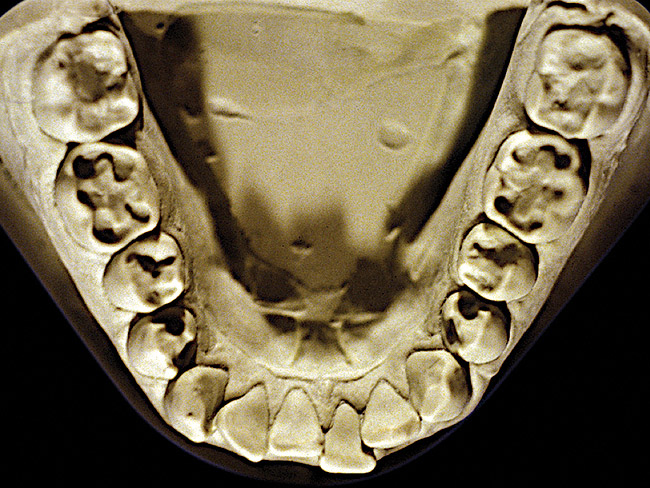

Figure 24 and Figure 25 exhibit NCLTS from fruit-mulling. The posterior teeth were affected to a greater extent than the anterior teeth, with the maxillary and mandibular posterior teeth affected equally, not only to each arch, but every tooth juxtaposed to each other. Cupping and cratering was present with abraded enamel edges from the mulling action. The diagnosis was confirmed from the pathognomonic pattern along with the match-up of abraded enamel edges peripheral to the cups and craters and the admission of the habit by the patient.

Figure 24  Moderate NCLTS from fruit-mulling, maxillary arch.

Figure 24

Figure 25  Moderate NCLTS from fruit-mulling, mandibular arch.

Figure 25